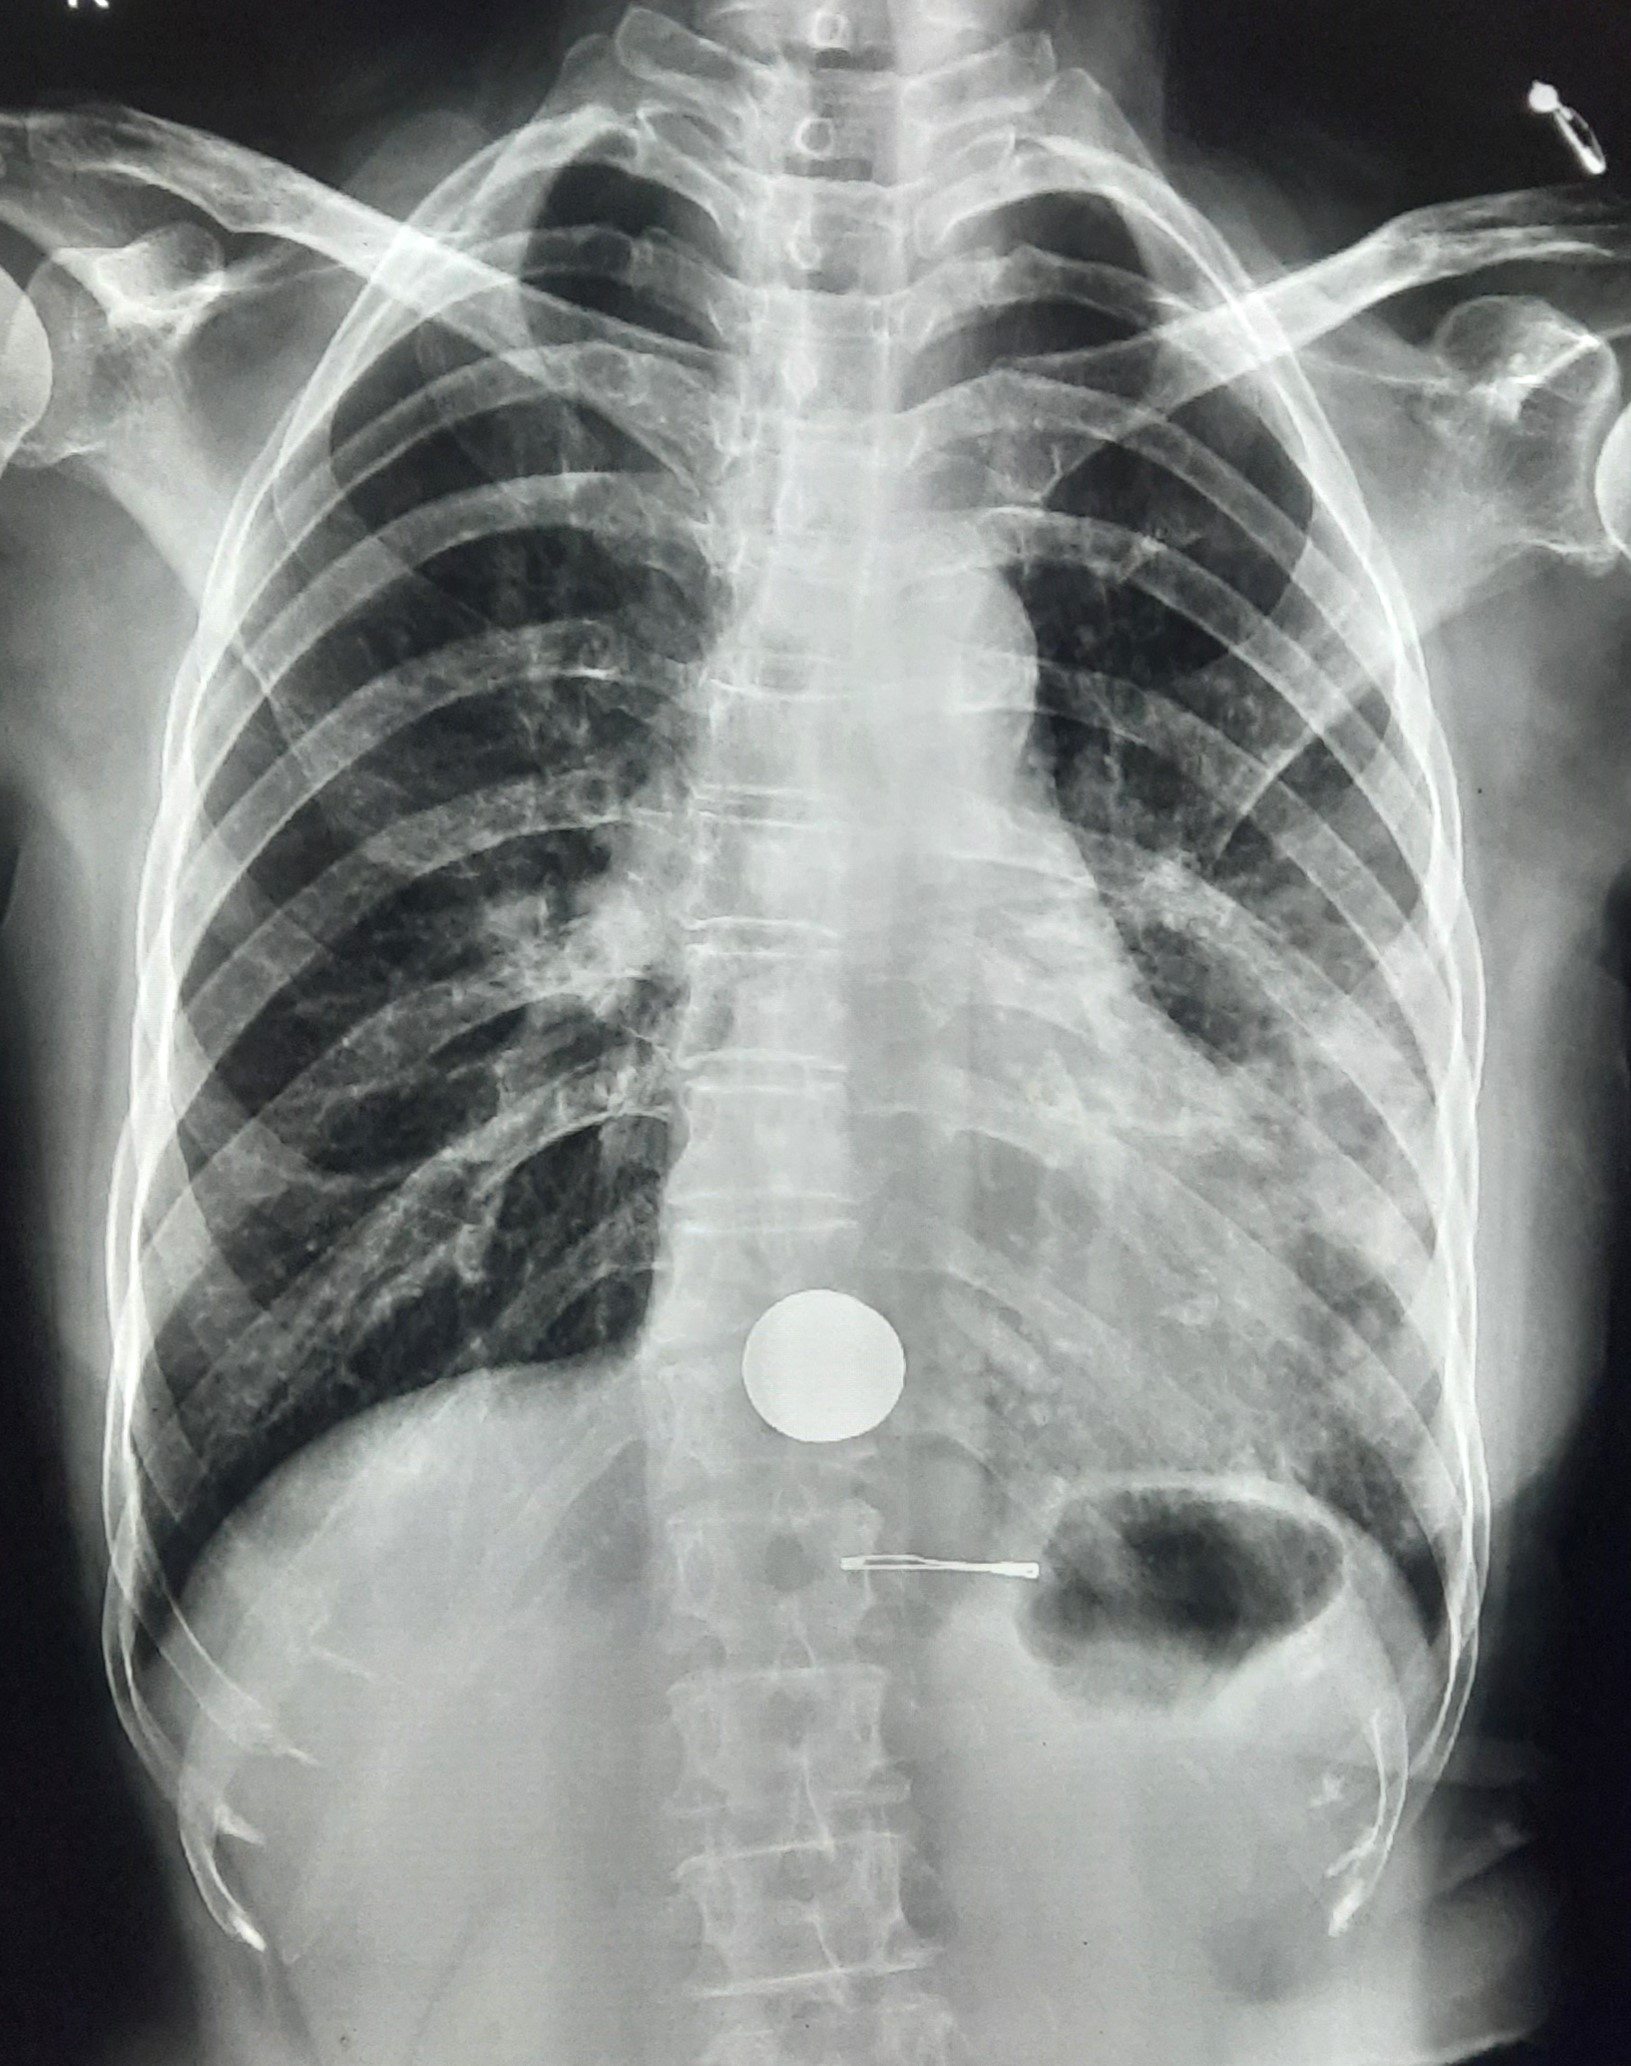

| 149 | IGGMC, Nagpur, Nagpur | P2 | 29-4323 | Samina Parveen | Consent taken on Paper | 30 Yrs. |

Provisional Diag : Bilateral Tubercular Pleural Effusion

Final Diag : Bilateral Tubercular Pleural Effusion With Right Sided Pigtail Infiltration |

TB Case (Confirmed) | Bilateral CP Angle Blunting With Bilateral Homogenous Opacity Left Zone With Pigtail Right Pleural Effusion | Abnormality visible on x-ray |